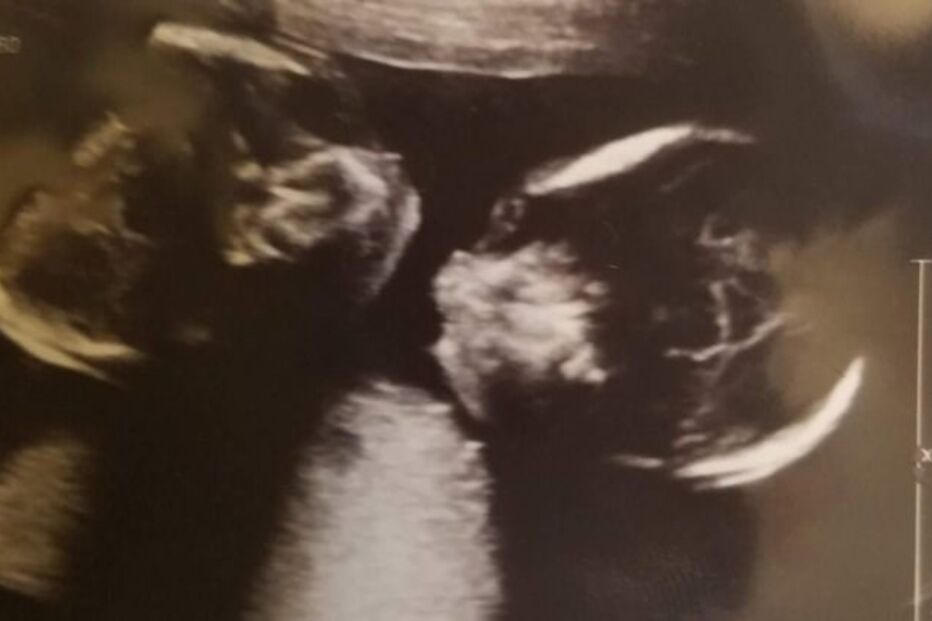

Bebés partilham coração e fígado. Médicos questionam a qualidade de vida futura das crianças.

Fuschia Gaskin e o marido, Quincy, ficaram eufóricos com a notícia que seriam pais pela segunda vez. A felicidade depressa deu lugar ao temor porque as bebés Lailani e Iyana, entre outras más formações, têm o mesmo coração e fígado. Ainda assim, a mãe das gémeas está expectante com o nascimento das filhas que acontecerá no próximo mês em New Jersey, e não hesitou em levar a gravidez até ao fim. Os médicos estão receosos receosos quanto à qualidade da vida futura das crianças.

Em novembro, a funcionária administrativa descobriu que estava grávida de gémeas. Os médicos detetaram algumas deformações nos fetos e pediram exames mais detalhados que concluíram que as gémeas têm vários problemas de saúde. As crianças partilham o fígado e o coração (condição que apenas afeta 1 em cada 200.000 bebés), e nunca vão poder ser separadas. Iyana possui um lábio leporino (fenda labial e do palato causada por anomalia congénita) e uma deformação no coração que altera a organização das cavidades do órgão.